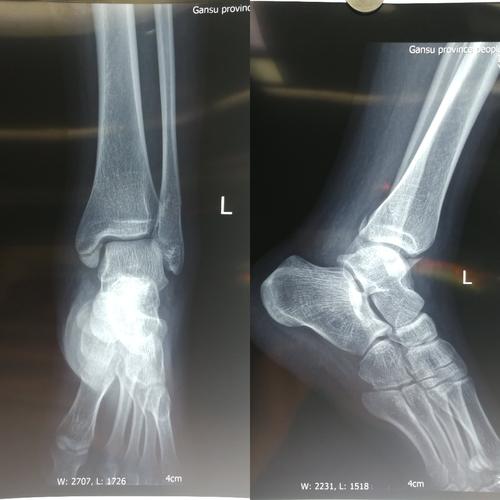

左踝关节骨折

踝关节骨折x光片

右踝关节骨折

正常踝关节片子图片

踝关节正侧位